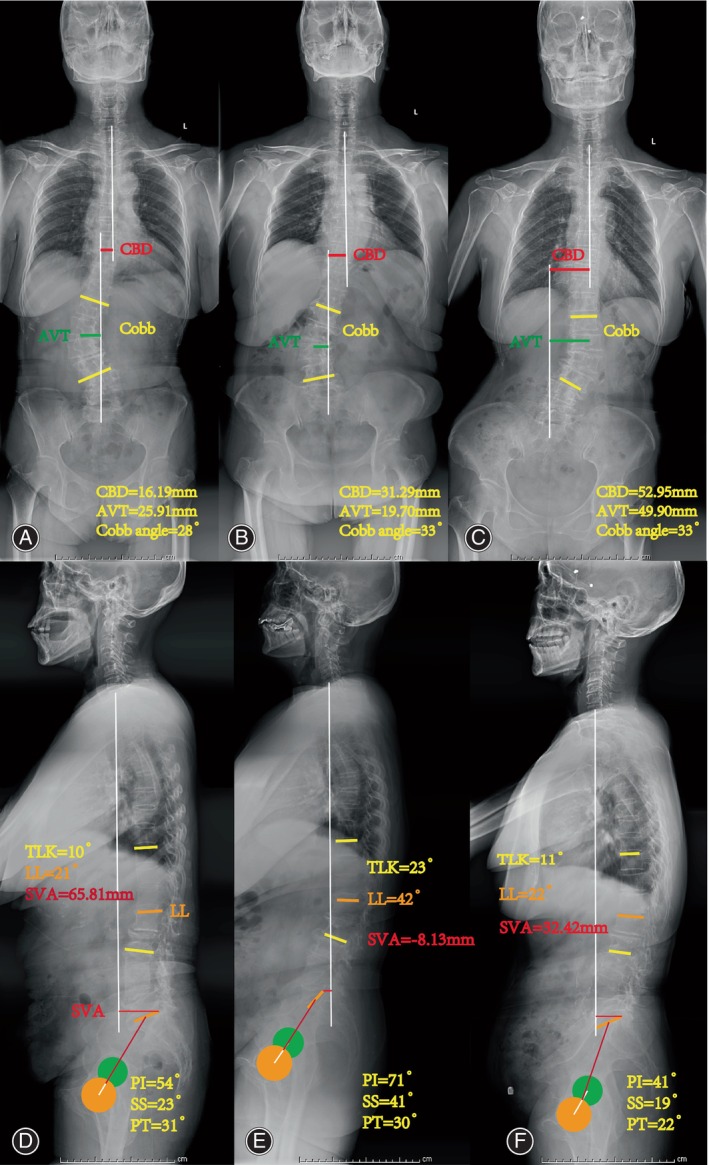

X‐ray Assessment

Bone structure parameters (Fig. 1), including Cobb angle, lumbar lordosis (LL), Loss of LL, CBD, thoracolumbar kyphosis (TLK), sacral slope (SS), pelvic incidence (PI), sagittal vertical axis (SVA), apical vertebral rotation (AVR), apical vertebral translation (AVT), direction of lateral bending, lumbar spondylolisthesis (LS) and T‐value were recorded and measured using neutral standing radiographs.ref. os14185-bib-0024

The primary curves consisted of thoracolumbar or lumbar curves. The additional curve included lumbosacral curves, and its direction was opposite to the primary curve. Type A was the most prevalent type, with more Type C patients than Type B patients (19.0% compared to 7.1%). There were no significant differences in terms of demographic and radiographic characteristics between three types as shown in Table 1. The number of vertebrae in the primary curve also showed no significant differences among the three subgroups (χ2 = 4.608, p = 0.294) as shown in Table 1. No significant differences were observed in terms of Cobb angle, PI, SS, PT, LL, TLK, SVA, AVT and LL loss, Kyphosis, LS, T‐value, L and R of main curve among the three subgroups in Table 2. However, the CBD in Type B and C patients was significantly greater than that in Type A.